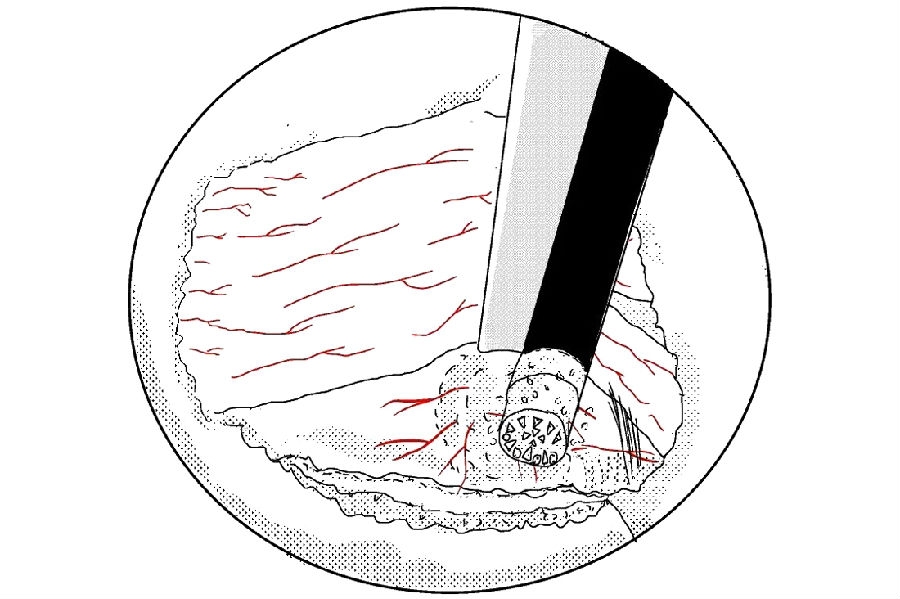

13. 使用髓核钳摘除突出的髓核组织;

14. 你可以选择使用等离子电凝皱缩来缩小裂口;

15. 或者是纤维环缝合修复;

16. 在手术最后放置引流是好习惯,最好放置于椎板表面,不至于干扰神经根。